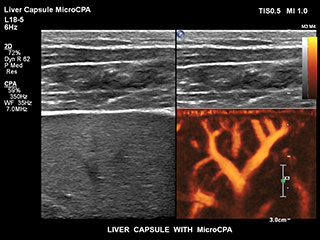

Bisher war die Erfassung von Flussdaten bei kleinen Gefässstrukturen mit niedriger Flussrate schwierig. Die neue EPIQ Funktion MicroCPA bietet eine schnelle und einfache Darstellung von Mikrozirkulation mit niedriger Geschwindigkeit und ermöglicht eine hohe Diagnosesicherheit bei der Beurteilung der Organperfusion oder von kleinen Gefässbetten.